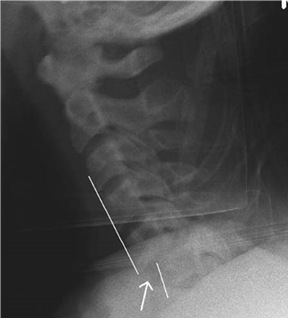

This 27-year-old has been involved in a road traffic accident (RTA).

Describe what you see in this picture and explain your initial management.

This is a clinical photograph showing an open fracture of the midshaft of the right tibia. After ruling out more urgent issues with an ATLS review, I would examine the wound, photograph it, and then cover it with a saline-soaked gauze. I would provide analgesia and splint the limb. I would give antibiotics and tetanus toxoid, if needed, and obtain AP and lateral radiographs.

When are you going to take this patient to theatre and what will you plan to do?

I would arrange for theatre at the earliest appropriate time (not necessarily <6 h). I would also discuss the case at an early stage with my nearest plastic surgical unit. I would perform an initial wash/scrub for gross contamination. I would then perform a thorough debridement of skin, fat, fascia, muscle, and bone. I would obtain fracture stabilization before further washout. I would apply dressings, splint the leg with the ankle plantegrade, and make a plan for future treatment.

What is your biggest concern in the early post-operative period and how do you monitor for this?

With any high-energy fracture, particularly tibial fractures, I would have a high index of suspicion for compartment syndrome. For this reason I would avoid regional anaesthetic blocks. In my unit we monitor patients with regular clinical observation. Invasive pressure monitoring is used for those patients who have a reduced level of consciousness.

How would you perform a lower leg fasciotomy?

I use the two-incision technique as described in the British Orthopaedic Association/ British Association of Plastic Surgeons (BOA/BAPS) guidelines published in 1997. The fi rst longitudinal incision is 1 cm medial to the postero-medial border of the tibia and allows decompression of the posterior compartments. The second incision is placed 2 cm lateral to the anterior border of the tibia and allows access to the anterior and peroneal compartments.

How soon should you aim to get soft tissue cover and what do you know about free fl aps?

The recommendation for defi nitive soft tissue cover is within 5 days of initial injury. Soft tissue coverage may be obtained by delayed primary closure or by one of the techniques of the reconstructive ladder. The most complex of these is the free fl ap. This usually involves taking a distant muscle with its vascular supply and revascularizing it with healthy vessels close to the recipient site. This muscle is then covered with a split thickness skin graft.